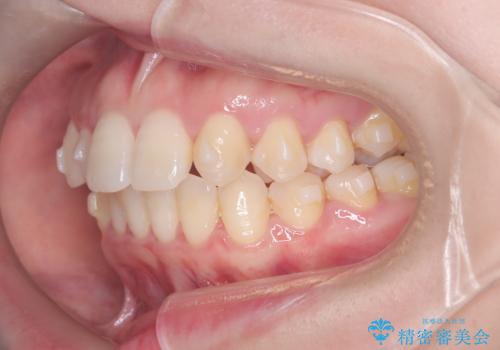

- 歯のデコボコと右上2番の歯の形が気になることを主訴に来院された患者様です。

軽度の叢生(凸凹)であったため、インビザラインのライトパッケージを用いて歯並びを改善しました。その後、右上2番はオールセラミッククラウンにより形態を回復し、審美性を向上させました。